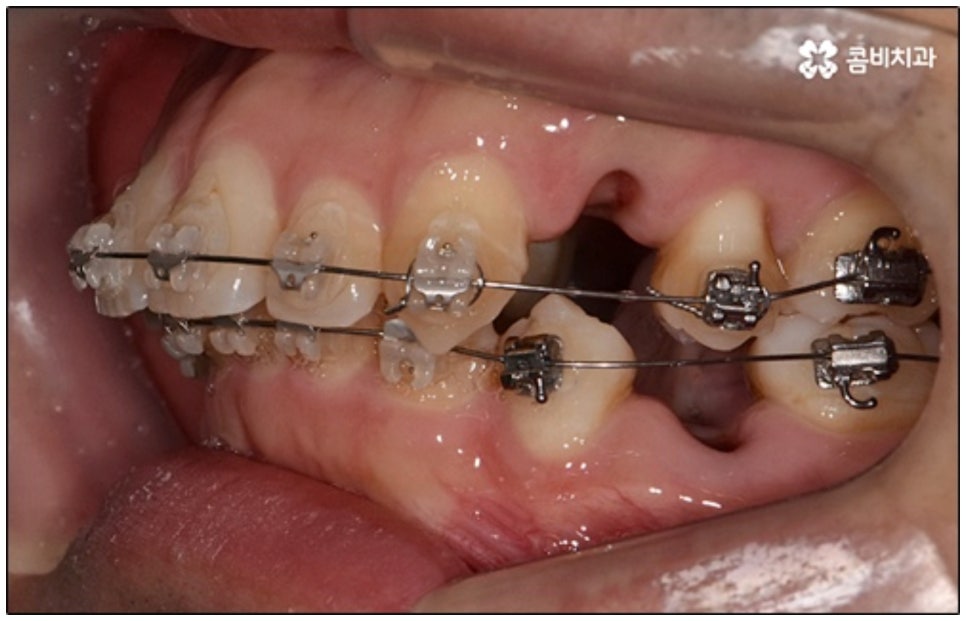

말씀드린 것과 같은 다양한 이점들이 있기 때문에 현재 본원의 교정 환자분들은 대부분 클리피씨교정 장치를 이용하여 치료를 진행하고 있습니다. 사진 역시 돌출입 교정을 위해 발치 후 클리피씨교정 장치를 이용하신 환자분의 케이스인데 시간이 지날수록 점차 앞니가 자연스럽게 들어가고 위아래 교합이 정확하게 맞아가는 것을 확인하실 수 있을 거예요.